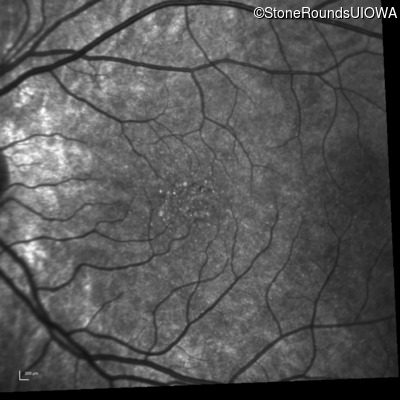

Infrared Fundus Photograph - Right - 20/50 +1 sc

Exemplar